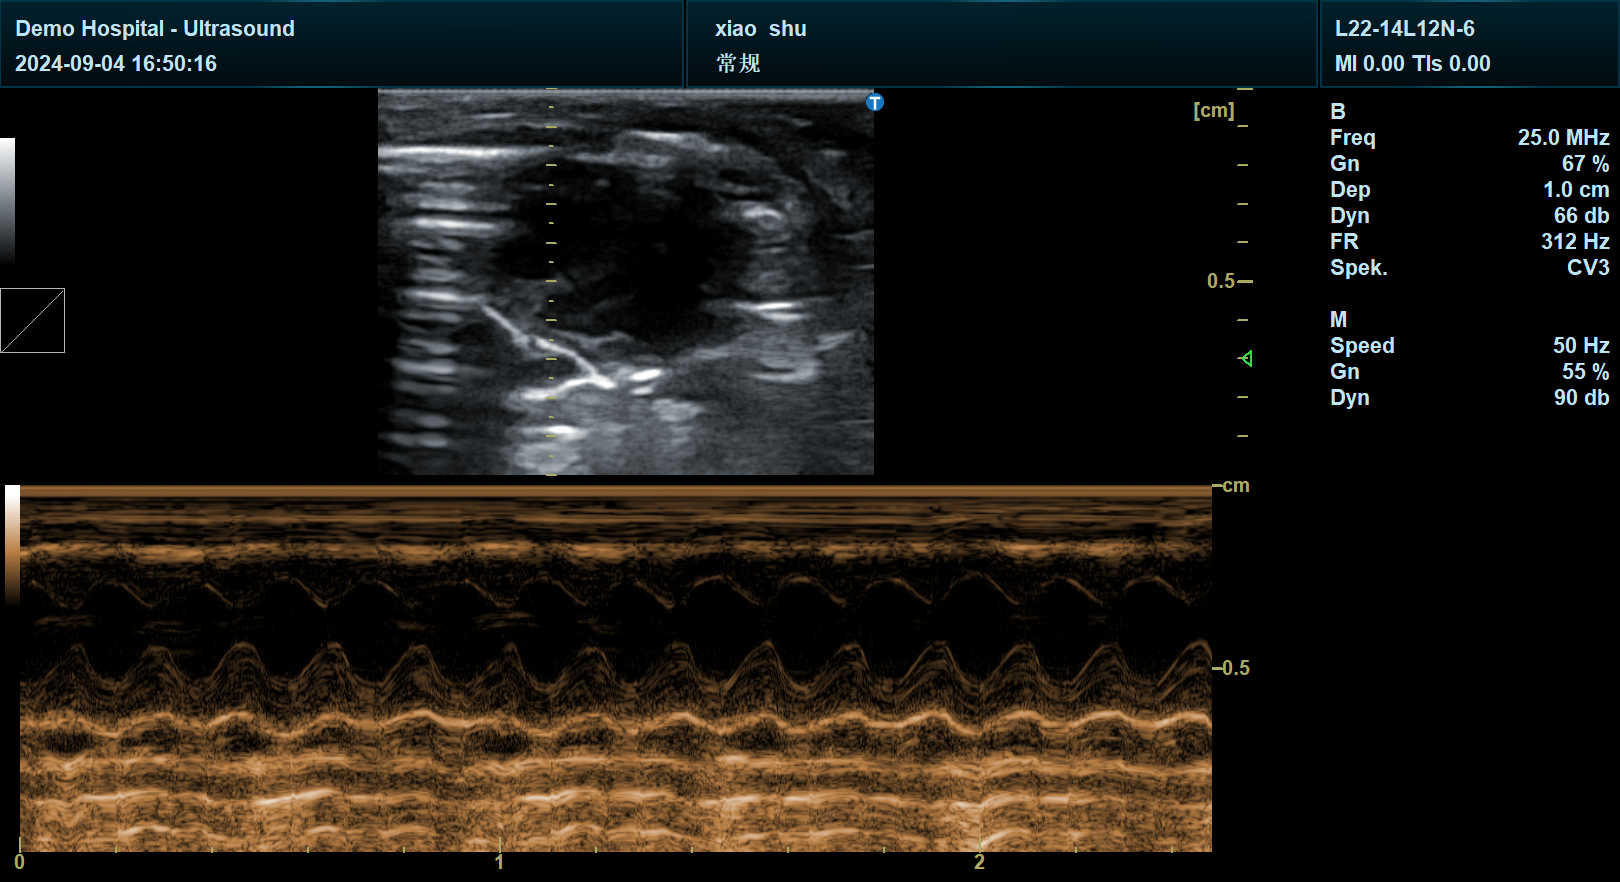

在心血管研究领域,宜慧康的心脏功能全模式覆盖(ECG+TVI、TVM、MAM、VCQ、CW、M型等)支持研究者对小鼠心脏进行从收缩/舒张功能到瓣膜运动、心肌应变的全维度分析。例如,在心肌梗死模型研究中,科研人员可通过宜慧康的应变成像技术量化心肌纤维化程度,结合血流频谱分析评估微循环障碍,为药物干预提供精准靶点。

宜慧康YHK-DY30专业版采用64通道电子相控阵探头,支持1-20MHz宽频带扫描,可灵活适配小鼠、大鼠、兔等实验动物的体型差异。其双屏液晶显示系统与触摸屏操作界面大幅简化复杂实验流程——研究者可在主屏实时观察高分辨率B超图像,同时在副屏调用血流动力学参数、组织弹性模量等量化数据,实现“观察-分析-记录”一体化操作。